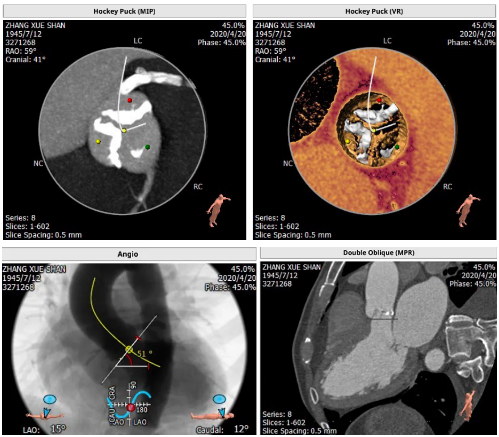

主动脉根部解剖: